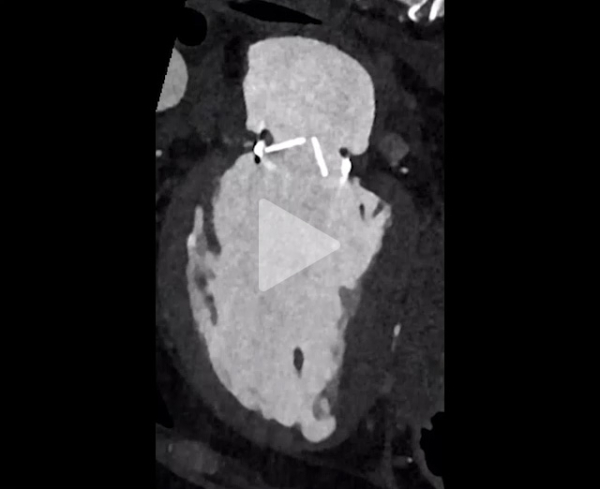

Scanner cardiaque

Vidéo 4

Vidéo 5

- Persistance du thrombus (discrète diminution) et blocage de l’ailette

- Absence d'élément de l'appareil sous valvulaire gênant la mobilité

- Bon fonctionnement de la prothèse aortique mécanique